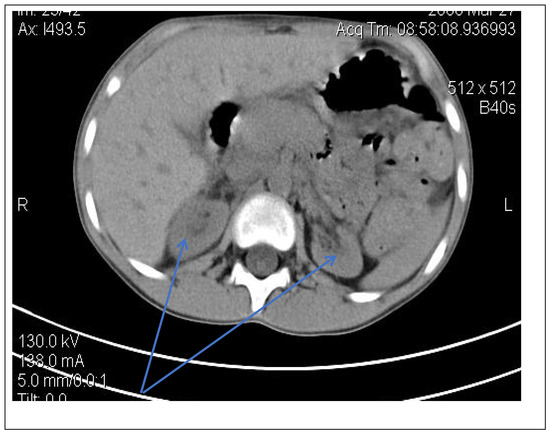

Due to the poor medical condition, with advanced renal failure, acidosis, arterial hypertension, the patient required the urgent initiation of hemodialysis. At the same time, we continued investigations for the etiology of renal failure (Table 1). We excluded the reflux nephropathy (secondary to primary or secondary vesicoureteral reflux, or posterior urethral valve) by voiding cystourethrogram (Figure 1).

Abdominal-pelvic computed tomography with contrast substance (Figure 2)

delayed and symmetrically reduced renal secretion

are described expansive renal formations replacing renal parenchyma and with a mass effect on it

Figure 2. Abdominal CT scan—expansive renal formations replacing renal parenchyma and with a mass effect (blue arrow).

Following the evaluations for the etiology of end stage renal disease (ESRD) we recommended abdominal ultrasound and CT scan. The abdominal ultrasound showed multiple homogenous hyperechoic nodular formations. The CT scan showed expansive renal formations replacing renal parenchyma, with a mass effect on it (Figure 2). We thought in that moment of a bilateral nephroblastoma, but the clinical and biological dates excluded it. There remained a possibility of extrapulmonary renal tuberculosis (due to his personal and family history). Even if the culture was negative for Koch Bacillus, while a value of 22 mm Palmer III—suggests tuberculin turn, the treatment was initiated according to the international guidelines [6] by the phthisiologist: triple combination of isoniazid, rifampicin and pyrazinamide in doses adjusted to his clearance, in the 7/7 scheme for 2 months, then isoniazid and rifampicin in the same doses 7/7 for another 7 months [6]. Two months after the initiation of the tuberculostatic treatment, a CT reevaluation was performed, which showed no changes in the renal formations, although biologically the inflammatory syndrome was absent. The child continued the chronic dialysis program and still had important palm-plant pain burning type. The suspicion of chronic glomerulonephritis with evolution towards end-stage renal failure remained, so, we decided to perform the kidney biopsy who showed Chronic glomerulonephritis with segmental and diffuse glomerular hyalinization (Table 1, Figure 3, Figure 4, Figure 5 and Figure 6).